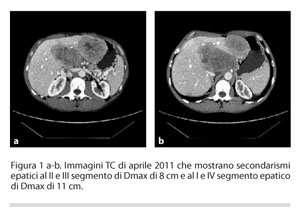

L’esame TC di stadiazione rilevava la presenza di secondarismi epatici sincroni al II e III segmento, di diametro massimo di 8 cm, e al I e IV segmento epatico di diametro massimo di 11 cm (figura 1a e 1b) oltre a linfomegalie mesenteriche. Venne quindi richiesta una valutazione dello status mutazionale di K-ras che risultò essere wild-type.